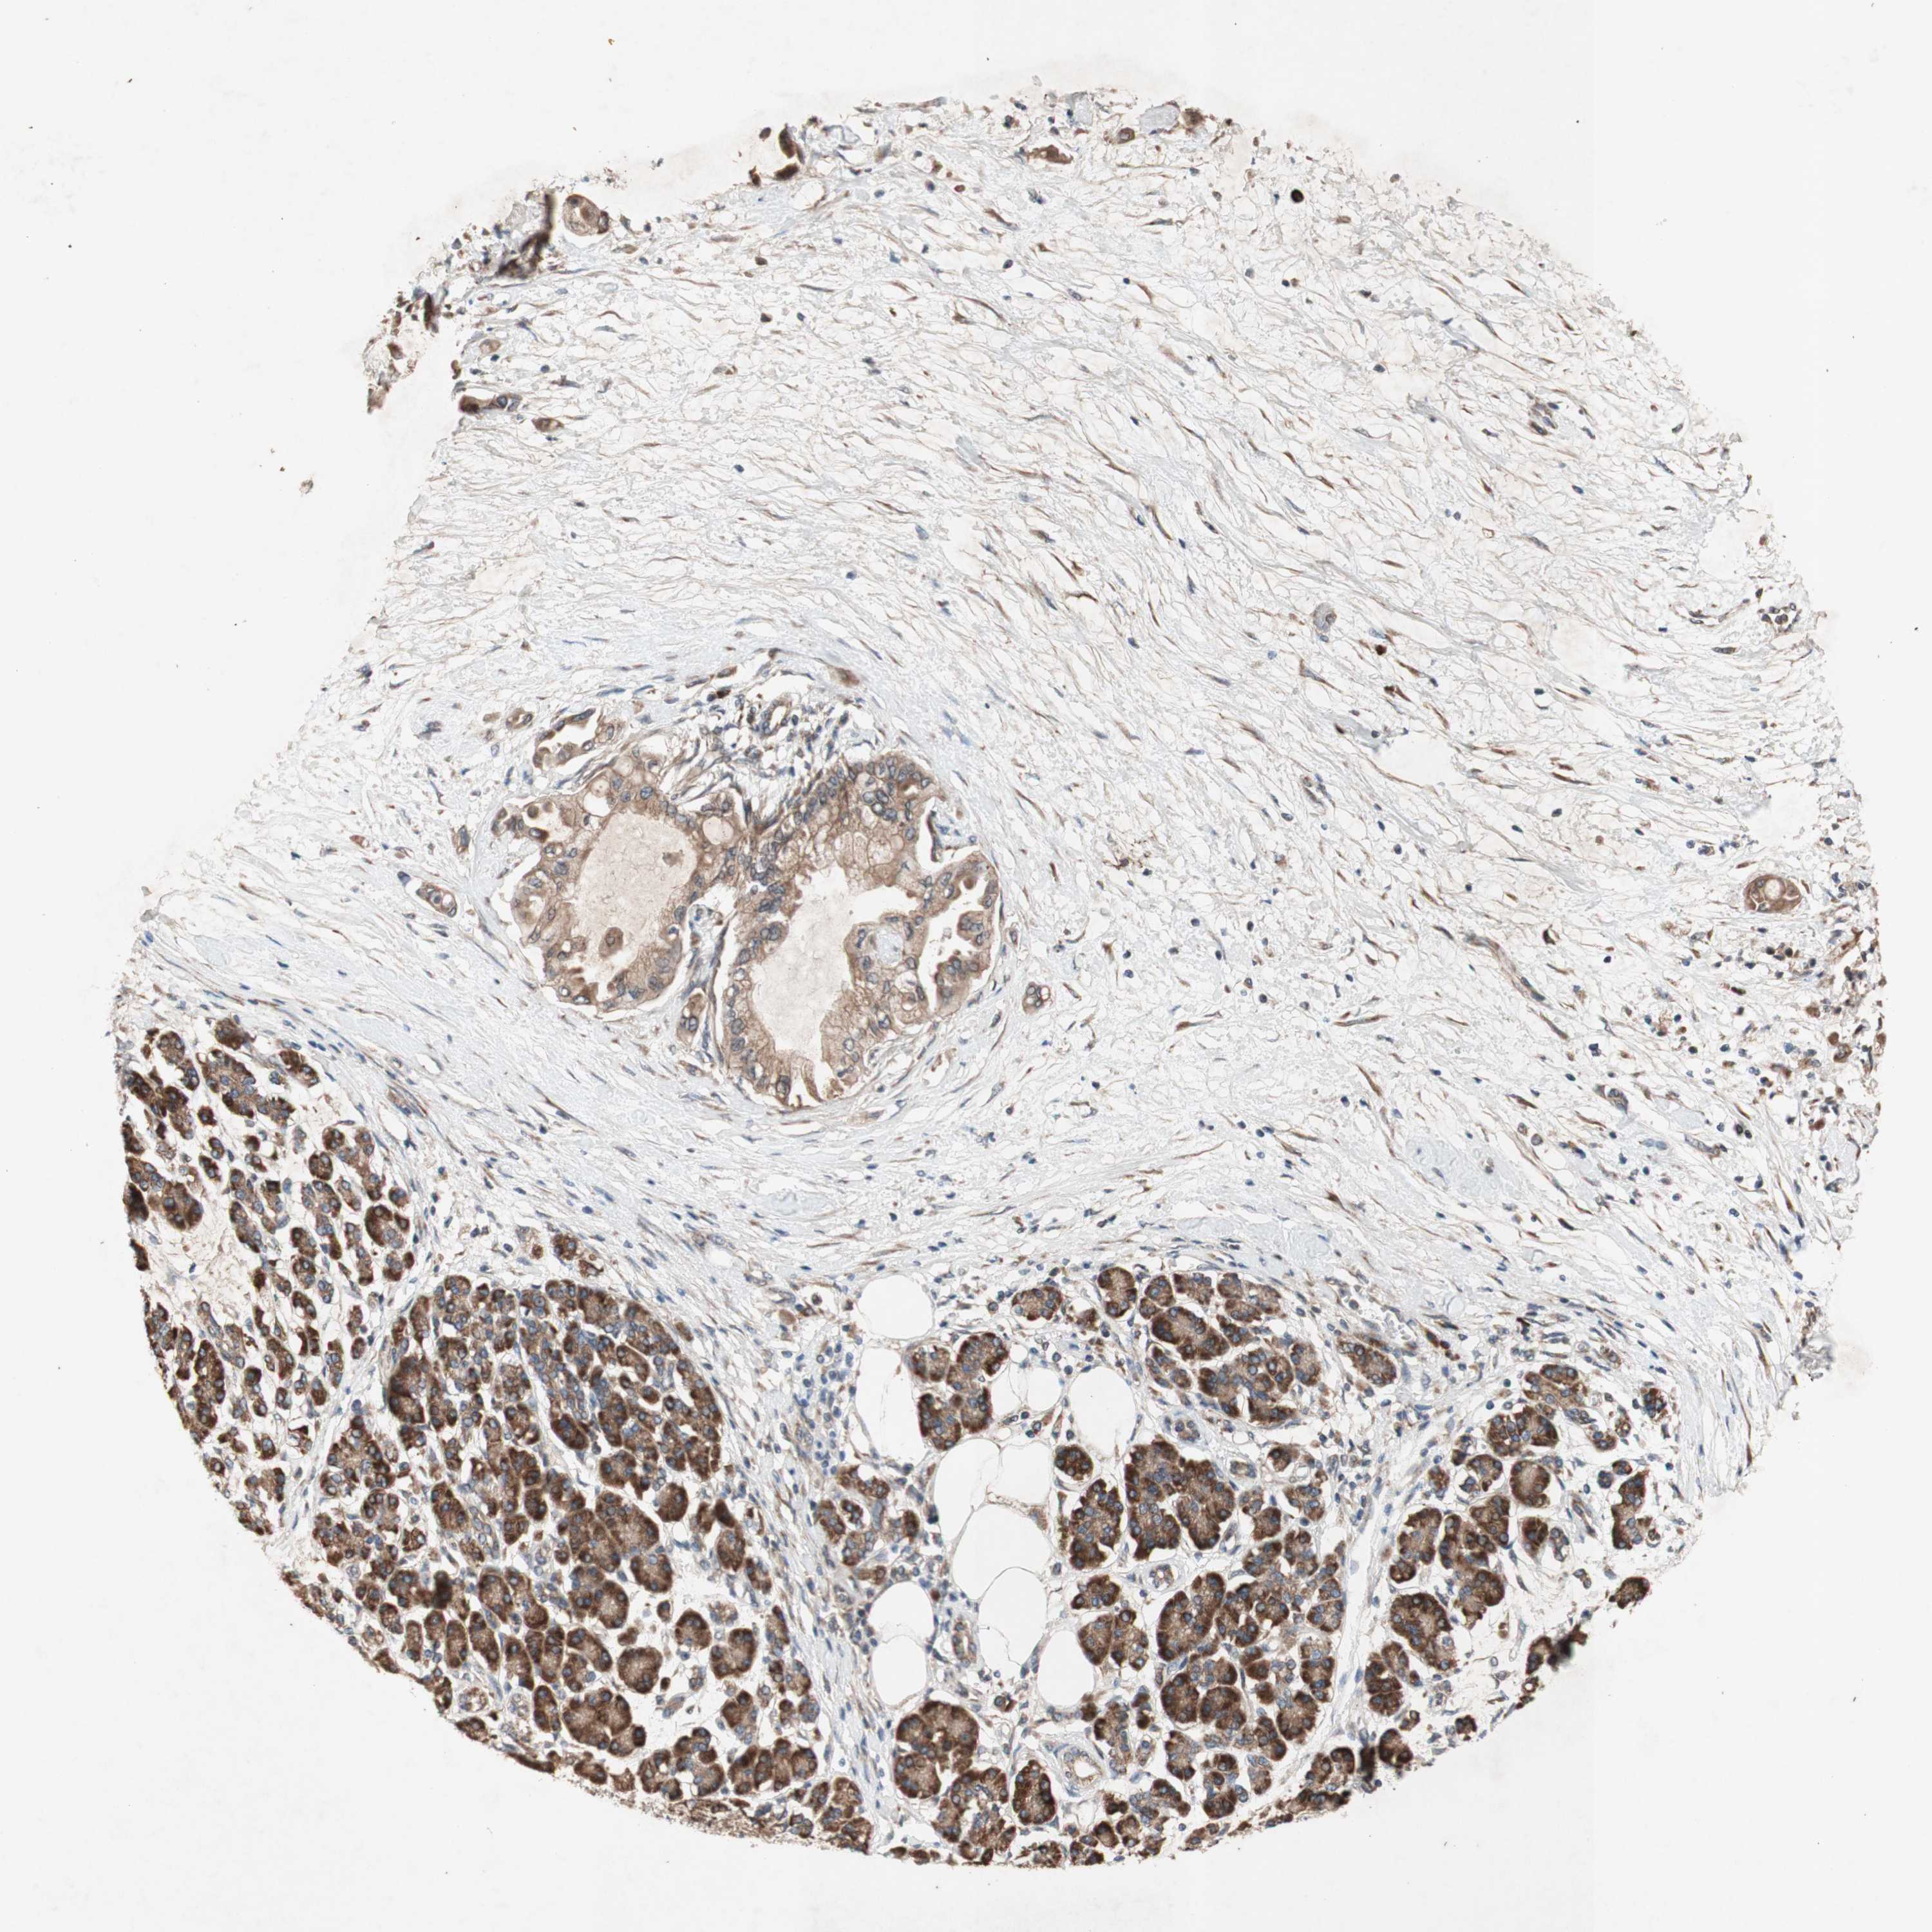

PANCREATIC CANCER - Protein expressioni

A mouse-over function shows sample information and annotation data. Click on an image to view it in a full screen mode. Samples can be filtered based on level of antibody staining by selecting one or several of the following categories: high, medium, low and not detected. The assay and annotation is described here.

Note that samples used for immunohistochemistry by the Human Protein Atlas do not correspond to samples in the TCGA dataset.

Antibody stainingi

Antibody staining in the annotated cell types in the current human tissue is reported as not detected, low, medium, or high, based on conventional immunohistochemistry profiling in selected tissues. This score is based on the combination of the staining intensity and fraction of stained cells.

Each image is clickable and will lead to virtual microscopy that enables deeper exploration of all samples and also displays staining intensity scores, fraction scores and subcellular localization as well as patient and tissue information for each sample.

Antibody HPA046841

Antibody HPA052867

Antibody CAB009746

Staining

High

Medium

Low

Not detected

Intensity

Strong

Moderate

Weak

Negative

Quantity

>75%

75%-25%

<25%

None

Location

Nuclear

Cytoplasmic/membranous

Cytoplasmic/membranous,nuclear

Adenocarcinoma, NOS

Adenocarcinoma, metastatic, NOS